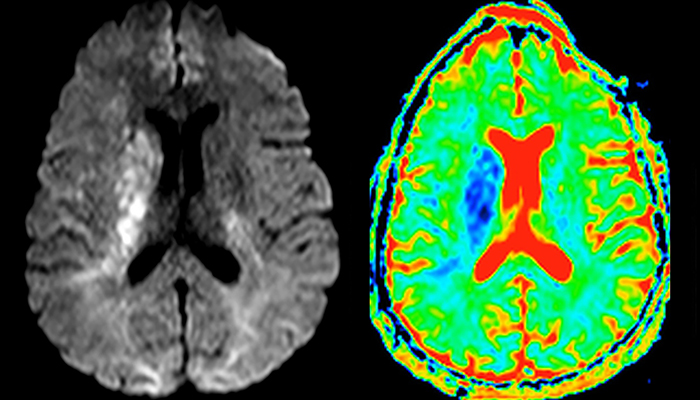

“In France, stroke is usually imaged with MRI, not CT, even for emergency treatment. This is because MRI helps us directly visualize ischemia in the acute phase, but can also help rule out differentials such as MS and hematoma. In addition, we can assess the intracranial and extracranial vessels during the same examination,” says Dr. Savatovsky.

The first challenge in MRI of stroke is speed. The patient typically arrives from an ambulance in the MRI preparation room and the installation is done on a separate dock outside the scanner room. “The venous access is placed during the neurological examination. If the delay from the first symptoms allows the patient to receive thrombolysis we do a very fast examination that typically lasts about 11 minutes including the pre-scans. In the case of transient ischemic stroke we usually add ASL perfusion because in some symptoms with negative diffusion, ASL sometimes indicates a vascular origin.”

“Ingenia provides great flexibility in the parameters setting. We can tune a sequence the way we want,” says Dr. Savatovsky. “For example, in a stroke exam we use a FLAIR sequence of about two minutes instead of the four-minute FLAIR we use for MS. The diffusion is 30 seconds, the T2*-weighted scan is 30 seconds, the angiography scan time is less than one minute. Ingenia is a great scanner in that situation; even with these fast sequences we can achieve good images with good SNR. When the first sequence tells us that it’s not an ischemic stroke but a hemorrhagic stroke, we may switch to a time-resolved angiography to look for vascular malformations and venous thrombosis.

“Every center is different, but for me the ideal protocol for stroke includes diffusion weighted imaging, FLAIR, and fast susceptibility imaging,” says Dr. Savatovsky. “Our fast susceptibility weighted imaging takes 50 seconds, so it’s as fast as T2*-weighted imaging. It visualizes hemorrhage but also the clots. We also do 3D MR angiography that provides information on cervical and brain vessels. If the patient does not need immediate treatment, or if additional information is needed to decide on treatment, we might also add perfusion imaging and post-contrast T1-weighted imaging.”